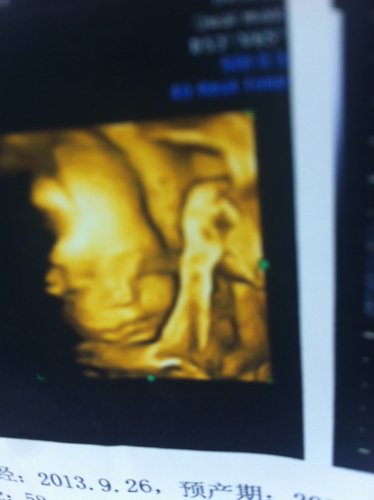

帮忙看下这两张四维彩超图有问题吗?是不是鼻子和眼睛不对劲啊?急急 点击展开 匿名用户 2014-04-07 12:16 为您推荐: 其他回答 病情分析: 您好,四维彩超上面就是这样的 指导意见: 如果自己有什么不明白的地方建议您最好还是咨询下自己的医生吧。 匿名用户 2014-04-07 16:26 相关问题 帮忙看下这两张是怀孕24周做的四维彩超图,感觉鼻子和眼睛有问题、你们认为有什么问题吗? 七个月的宝宝鼻子上眼睛上怎么像张斑是的 胎儿颜面可显示是不是鼻子和眼睛就没有问题